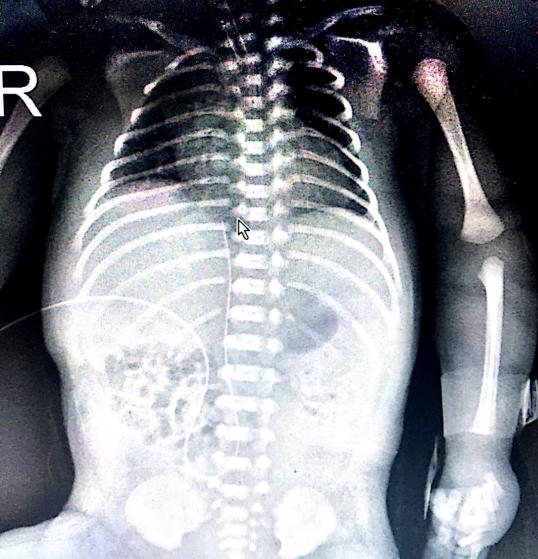

目前脐静脉置管术已经成为国内外NICU救治早产儿的常规技术,脐静脉通路被认为是早产儿生命初期极其重要的生命通道。UVC以置入下腔静脉为目标, 导管尖端位置位于下腔静脉中上1/3或者下腔静脉与右房交界处,膈肌上下1cm处,为最佳位置。相对应的约为8-10胸椎(图二为第9胸椎)。但如果导管尖端位置不当,会引起严重并发症:如位置过深可引起心律失常, 心包积液、心包填塞等;如位置过浅或者入肝内, 可以造成肝坏死,坏死性小肠结肠炎等。因此对脐静脉置管导管尖端位置进行精准定位非常重要。

图一:X摄片显示导管尖端位置(T9)